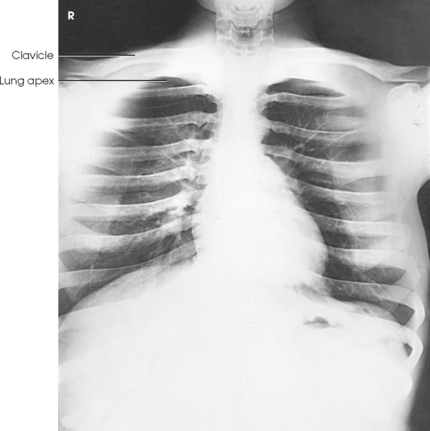

For radiography of the heart and lungs, the patient is placed in an upright position whenever possible to prevent engorgement of the pulmonary vessels and to allow gravity to depress the diaphragm. Of equal importance, the upright position shows air and fluid levels. In the recumbent position, gravitational force causes the abdominal viscera and diaphragm to move superiorly; it compresses the thoracic viscera, which prevents full expansion of the lungs. Although the difference in diaphragm movement is not great in hyposthenic individuals, it is marked in hypersthenic individuals. Figs. 10-10 and 10-11 illustrate the effect of body position in the same patient. The left lateral chest position (Fig. 10-12) is most commonly employed because it places the heart closer to the IR, resulting in a less magnified heart image. Left and right lateral chest images are compared in Figs. 10-12 and 10-13.

Structures shown: PA projection of the thoracic viscera shows the air-filled trachea, the lungs, the diaphragmatic domes, the heart and aortic knob, and, if enlarged laterally, the thyroid or thymus gland (Fig. 10-32). The vascular markings are much more prominent on the projection made at the end of expiration. The bronchial tree is shown from an oblique angle. The esophagus is well shown when it is filled with a barium sulfate suspension.